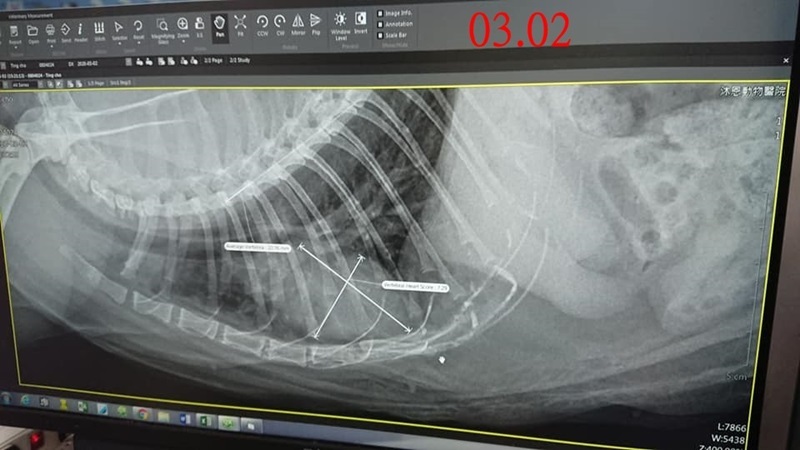

2020年的2月,照護員發現定著的肛門腺液很多、有些流血,約診檢查發現有阻塞情形,醫師幫定著擠乾淨肛門腺,研判是發炎腫脹導致的阻塞,吃藥並於一週後再回診追蹤,肛門腺已消腫,只剩一點點液體,因定著時有咳嗽情況,再開口服抗生素及化痰藥,一週後回診查看咳嗽情況,拍攝X光沒有發現腫瘤或心臟問題,可能是支氣管炎所致,續吃抗組織胺及化痰藥希望可以改善,並指示須要記錄體重。

本筆醫助是定著於2月份及3月2日至沐恩醫院的醫療費用,包含肛門腺治療、X光、用藥,請大家一起幫忙可愛的定著,謝謝大家。

3/02 定著 沐恩回診 楊醫師

體重: 5.305 kg 2/17 5.450kg

一、看診情形

醫師檢視近2次X光影像研判咳嗽原因,應是慢性支氣管炎,沒有腫瘤或心臟問題,咳嗽症狀沒有很嚴重,不需要吃類固醇,用化痰和抗組織胺控制就好,因是慢性的支氣管炎,所以會偶發性咳嗽,兩週停藥觀察咳嗽有無改善,停藥後若是症狀沒改善,就再繼續吃,嚴重才會建議給予類固醇,因體型較胖,醫師擔心若是服用類固醇,也可能造成體重上升,需要每週紀錄體重變化,若是飲食正常體重還下降,則可能不正常,需要回診驗血檢查。

二、用藥⚠️ 有更動!

1. 化痰+抗組織胺:每天2次,每次一顆。

2. 每週一紀錄體重一次。